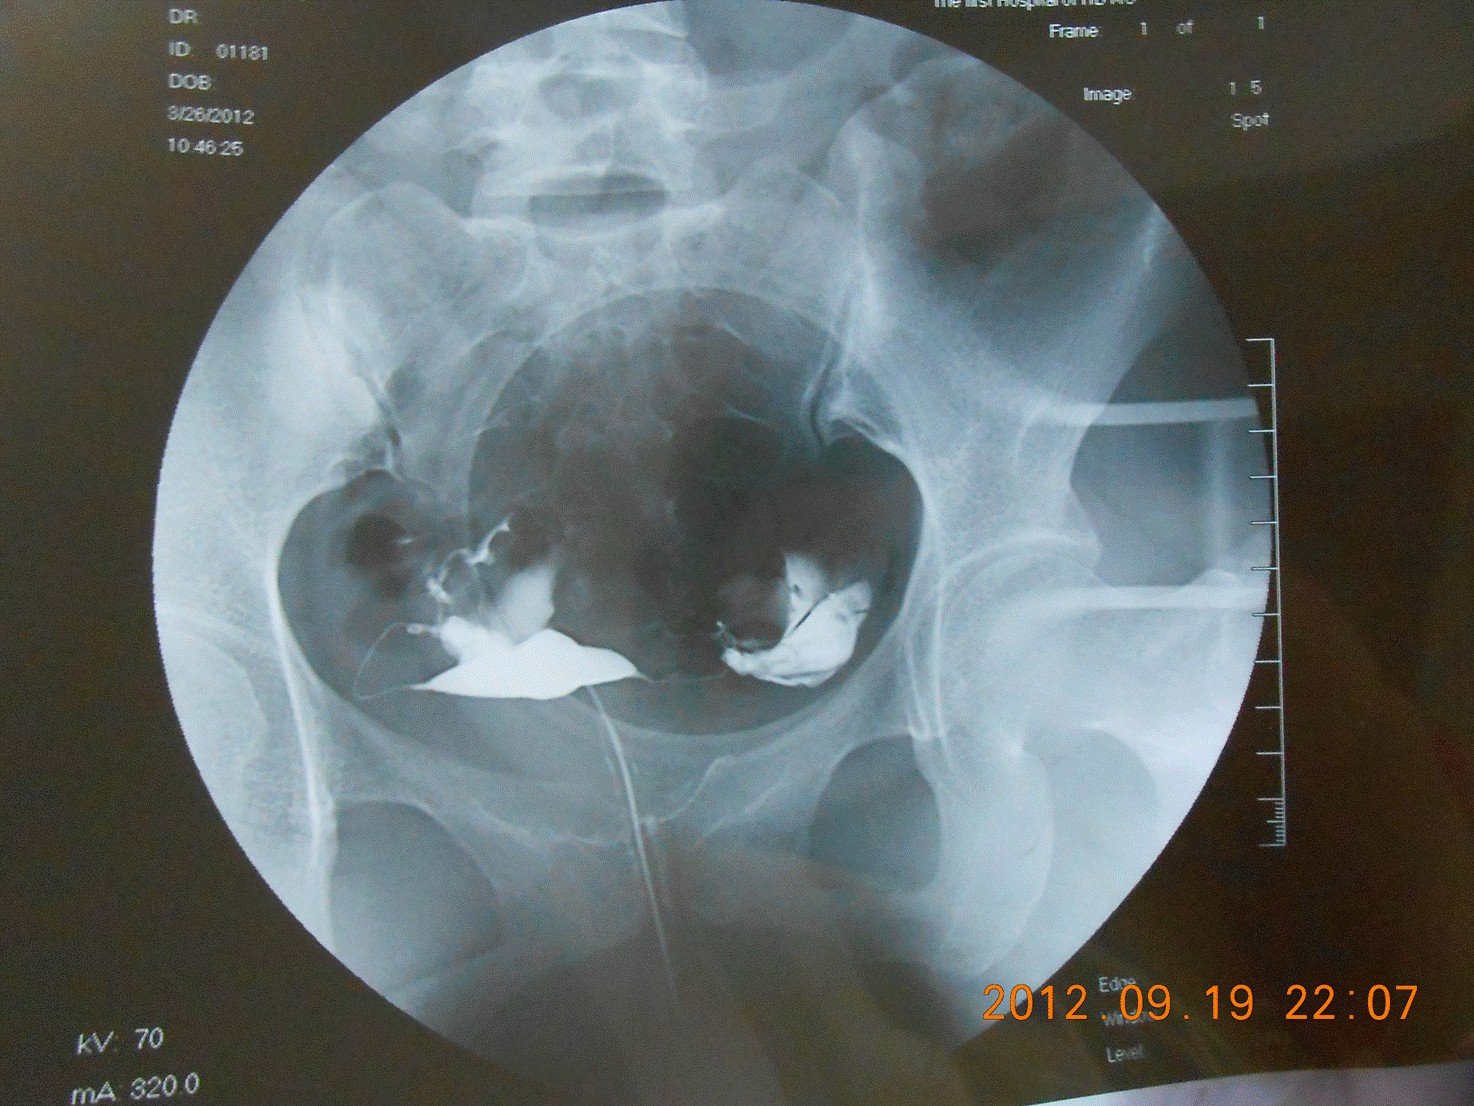

这是我半年前做的输卵管造影,由于没有延迟片,可能不太正规,但烦请知情者告知能反应的情况,万分感谢!

我感觉这两个管子都是不通的,或是通而不畅。看不清楚,但最大的原因是这个手术没成功,不光是没有延迟片,而是给药不足。

你好! 从片子看,右侧输卵管通而不畅,左侧输卵管远端阻塞。